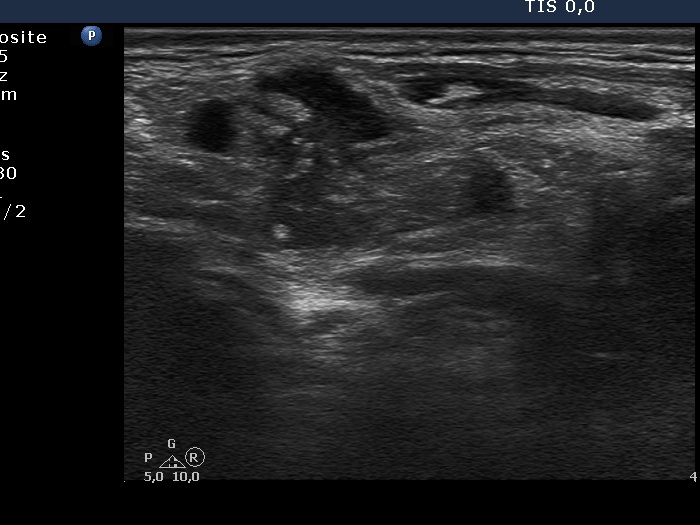

Ultrasonography: The thyroid was intact. There were multiple nodes in both supraclavicular regions. The nodes presented an absolutely irregular shape and border. They contained numerous hyperechogenic circumscribed areas.